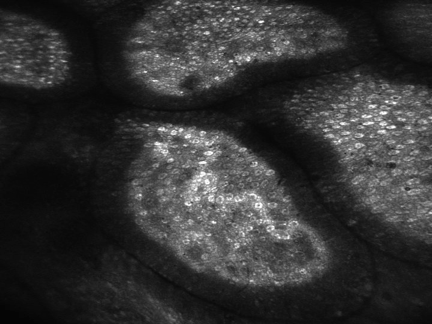

A endomicroscopia confocal é um nova técnica endoscópica que permite a obtenção de imagens de alta-resolução da camada mucosa do trato gastrointestinal. Esta técnica baseia-se na iluminação da mucosa com um laser, que é absorvido por um agente fluorescente, sendo depois a luz refletida captada. O laser é focado a uma profundidade selecionada no tecido de interesse e a luz refletida é então reorientada para um sistema de deteção pela mesma lente, excluindo-se a luz refletida de outros pontos da mucosa. Isto aumenta drasticamente a resolução espacial das imagens obtidas, captando-se imagens muito ampliadas e de alta resolução. Através desta técnica podem observar-se durante o procedimento de endoscopia, estruturas celulares e subcelulares com extremo detalhe, tal como num microscópio convencional (ver figuras 1 a 3).

Figura 1. Imagem de mucosa gástrica normal obtida através de endomicroscopia confocal

Figura 2. Imagem de mucosa normal do intestino delgado obtida através de endomicroscopia confocal

Figura 3. Imagem de mucosa normal do intestino grosso (cólon) obtida através de endomicroscopia confocal